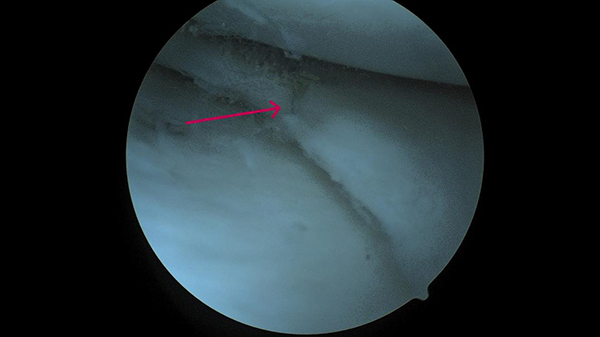

▲红色箭头所示为应用缝合器技术缝合撕裂后的半月板

术后患者感觉右膝关节疼痛明显缓解。